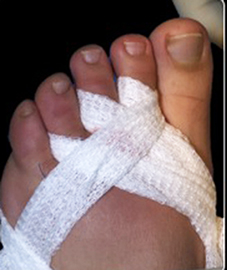

Una vez realizada la osteotomía, las incisiones se suturaron con monofilamento 0000. Se utilizó un vendaje para realizar tracción en los dedos de los pies en dirección medial con una cincha metatarsiana. El paciente salía de quirófano andando con un zapato quirúrgico de suela rígida y plana. Las suturas se retiraron a los siete días y se le mostró cómo cambiar el vendaje para el lavado diario. Se insistió que no debían caminar descalza, sin calzado ni vendaje, para evitar el desplazamiento de las osteotomías (Figura 2).

Figura 2a

Figura 2b

Figura 2. Técnica quirúrgica a) osteotomía DMMO percutánea, b) imagen fluoroscópica de las osteotomías, c) sutura, d) vendaje postquirúrgico con cinchas invertidas para mantener la alineación de los metatarsianos, d, e) vendaje definitivo postquirúrgico, f) paciente al salir de quirófano con apoyo completo y zapato de suela plana y recta